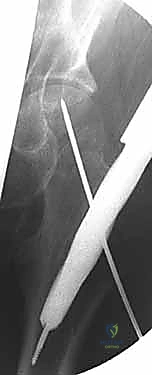

التثبيت بالمسامير المجوفة عبر الجلد (Percutaneous Cannulated Screws): ثورة في جراحة العظام

تُعد تقنية التثبيت باستخدام المسامير المجوفة (Cannulated Screws) المعيار الذهبي لعلاج كسور عنق الفخذ غير المزاحة (Garden I & II) لدى جميع الأعمار، والكسور المزاحة التي يمكن ردها بنجاح لدى الشباب والبالغين.

ما هي المسامير المجوفة (Cannulated Screws)؟

هي مسامير طبية متطورة مصنوعة من التيتانيوم (Titanium) أو الفولاذ المقاوم للصدأ (Stainless Steel). السمة المميزة لها هي وجود "تجويف" أو نفق يمتد عبر مركز المسمار بالكامل. هذا التصميم العبقري يسمح للجراح بإدخال سلك توجيهي رفيع (Guide Wire) أولاً في العظم لتحديد المسار الدقيق، ثم يتم تمرير المسمار المجوف فوق هذا السلك لينزلق مباشرة إلى المكان المحدد بدقة مليمترية.

مميزات التثبيت عبر الجلد (Percutaneous Technique)

- تدخل جراحي طفيف (Minimally Invasive): لا يتم عمل شق جراحي كبير لفتح العضلات والأنسجة، بل يتم إدخال المسامير عبر شقوق جلدية صغيرة جدًا (حوالي 1-2 سم لكل مسمار).

- الحفاظ على التروية الدموية: عدم فتح محفظة المفصل يقلل من خطر الإضرار بالأوعية الدموية المتبقية التي تغذي رأس الفخذ.

- ألم أقل بكثير: نظرًا لعدم قطع العضلات الكبيرة، يكون الألم بعد العملية في حده الأدنى.

- شفاء أسرع: خروج أسرع من المستشفى وتأهيل حركي مبكر.